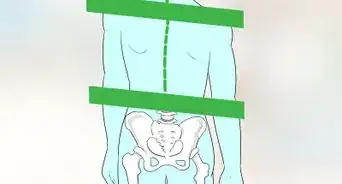

3Locate the spinal canal that holds nerves and fluid. Behind the column of vertebrae and discs, you'll see a long canal that holds nerves and spinal fluid. It will either be bright white or dull gray depending on whether you have a T1 or T2 image.[8]

- If you have normal alignment, the canal will be solid, as though you could draw a straight line down the vertebrae and discs of your spinal column. The line naturally curves at the lower end of the lumbar region.

4Draw a line down the vertebrae to check your alignment. Looking at the sagittal image, the edges of your vertebrae flowing down your spine should be even if you have normal alignment. If any of the vertebrae are protruding beyond the others, so that the line isn't smooth, this may be the cause of some of your symptoms.[13]

- Your spine has a natural curve at L4 and L5, so it won't be a straight line all the way down. However, the line you draw (including the curve) should still be smooth and even.

- It's easier to see this if you're looking at a T2 image, in which the spinal canal will be a bright white compared to the rest of the image.